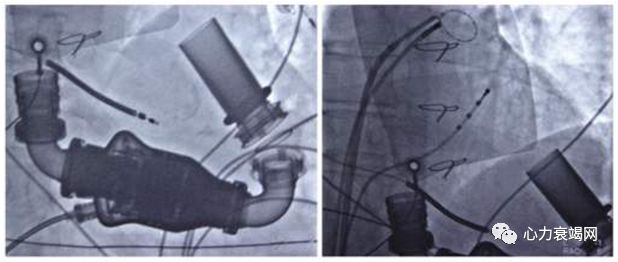

6名心衰 (61±7岁, LVEF 26±7%)伴持久性房颤者(DCM 5例、ICM 1例),心功能III-IV级,均无左室内传导阻滞,2名有肾功能不全。消融术后5名DCM患者的LVEF和心功能明显改善(56±4%, 心功能I-II)不再需要ICD治疗,缺血性心肌病患者的心功能改善,但LVEF变化不明显(30%)植入ICD。随访18个月,所有患者均为窦性心律,其中4名DCM 和1名ICM患者行2次手术。

Bortone A, et al. Sinus rhythm restoration by catheter ablation in patients with long-lasting AF and congestive heart failure:impact of the LVEF improvement on the ICD insertion indication. Europace. 2009;11(8):1018-23

PVI+Roof/MA/TA消融线手术时间210分钟,消融70分钟随访10个月,ICD监测未发现房性心律失常,患者病情稳定。